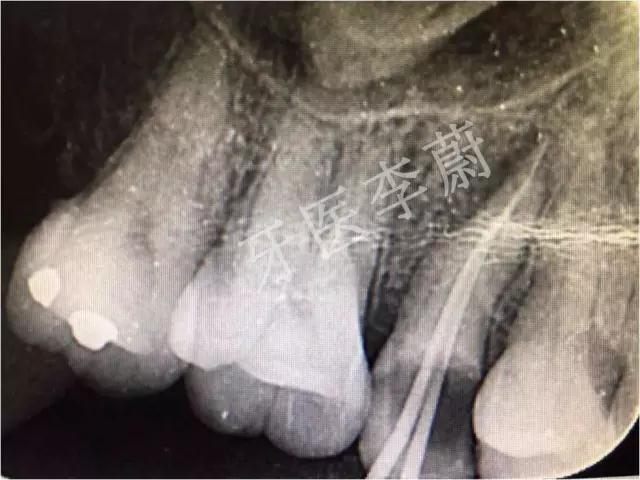

X片示:15残冠影,根尖有骨密度降低影。

局部X牙片